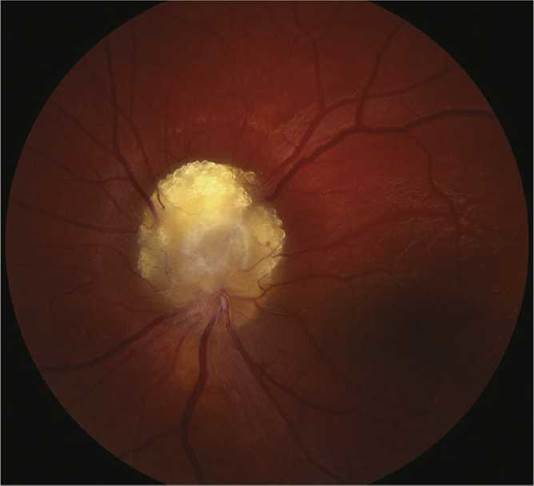

(See Figures 13.13.4 and 13.13.5.)

FIGURE 13.13.4 Retinal astrocytic hamartoma.

Ocular. Astrocytic hamartoma of the retina or optic disc (a white, semitransparent, or mulberry-appearing tumor in the superficial retina that may undergo calcification with age; no prominent feeder vessels; no associated retinal detachment; often multifocal and bilateral) and punched-out chorioretinal depigmentation.